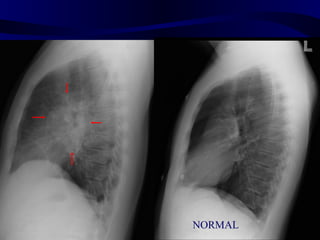

Tension Pneumothorax

ptxinspexp

Inspiration                Expiration